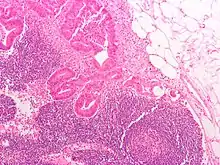

Definitive staging can only be done after surgery and histopathology of colorectal carcinoma. An exception to this principle would be after a colonoscopic polypectomy of a malignant pedunculated polyp with minimal invasion. Preoperative staging of rectal cancers may be done with endoscopic ultrasound. Adjunct staging of metastasis include abdominal ultrasound, MRI, CT, PET scanning, and other imaging studies.